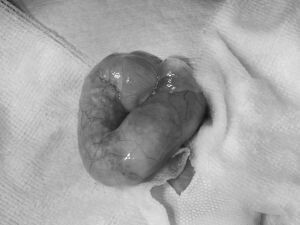

全身麻酔をかけてお腹を開けると、腹筋が破れて巨大な腸管が飛び出しており、中には大量の砂が詰まっていました。

詰まっていた砂は全て取り出し、開いていた腹筋の穴を縫い合わせて手術終了となりました。